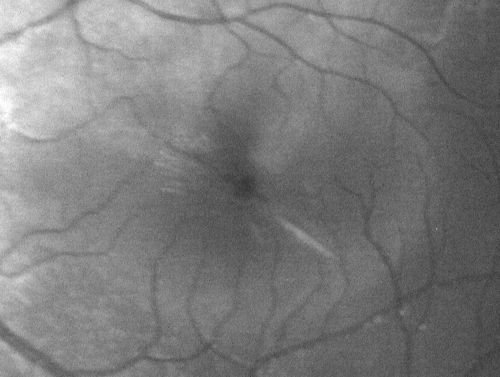

Macular Hole - Traumatic - 11 year old boy (also retinal whitening Berlins Edema)

11-year-old boy with a history of blunt trauma to the left eye yesterday.  He reports he lost vision immediately but it has gotten somewhat better.  He reports he sees “red streamers” and he has very blurry visual acuity., 20/200 OS